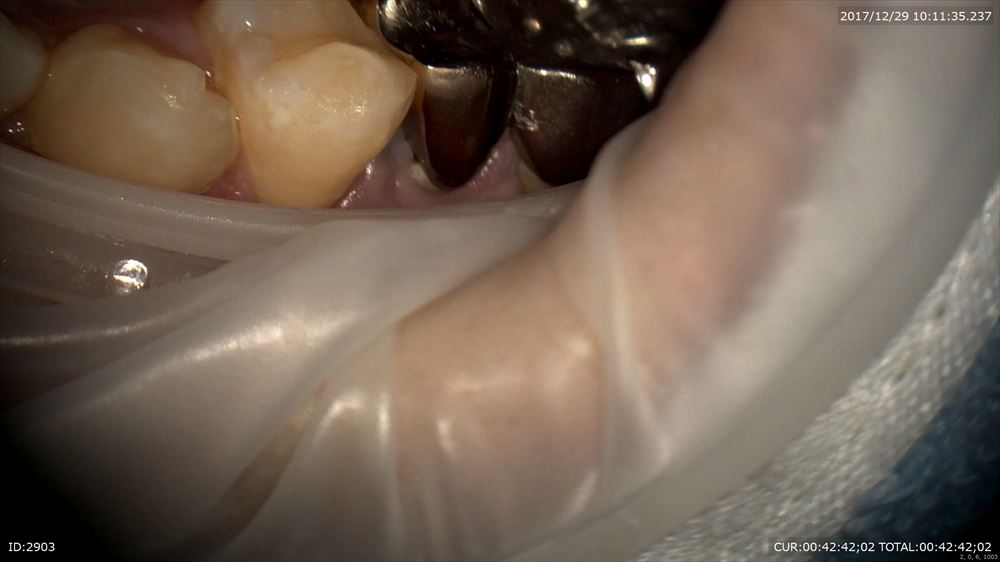

ラバーダムをして

デブライドメント